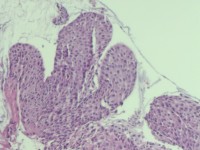

性别

女

年龄

38岁

临床诊断

宫颈病变

一般病史

宫颈癌筛查:HPV52(+)

标本名称

宫颈6点组织

大体所见

灰白色组织1块

可以诊断CIN几级

图4

HSIL(CIN3)累腺